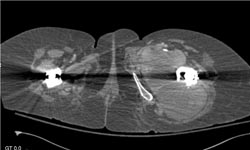

Lymphoma Involves Spine and Pleura